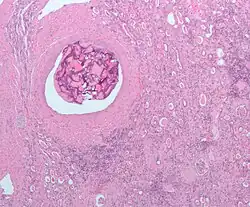

Histopathologische (van ziek weefsel) afbeelding van niercelkanker. Monster (deel van weefsel) na nefrectomie. Hematoxyline-eosinekleuring | ||||

Bij licht-microscopisch onderzoek is te zien dat de tumorcellen samenklonteren tot strengen, papillen, buisstructuren of nestjes. De individuele cellen zijn atypisch (afwijkend van de normale structuur van de niercel), polygonaal (veelhoekig) en groot. Omdat de cellen glycogeen en lipiden opslaan in het cytoplasma zien ze er helder (Engels: clear), vetbeladen uit; de celkern blijft centraal in de cel, de celmembraan is duidelijk zichtbaar. Sommige cellen zien er kleiner uit met eosinofiel cytoplasma en lijken op normale tubuluscellen. Het stroma, het omringende bindweefsel van het gezwel, is verminderd, maar wel gevacuoliseerd (met vacuolen). De tumor drukt op het omringende parenchym van de nier en vormt een pseudokapsel.[24]